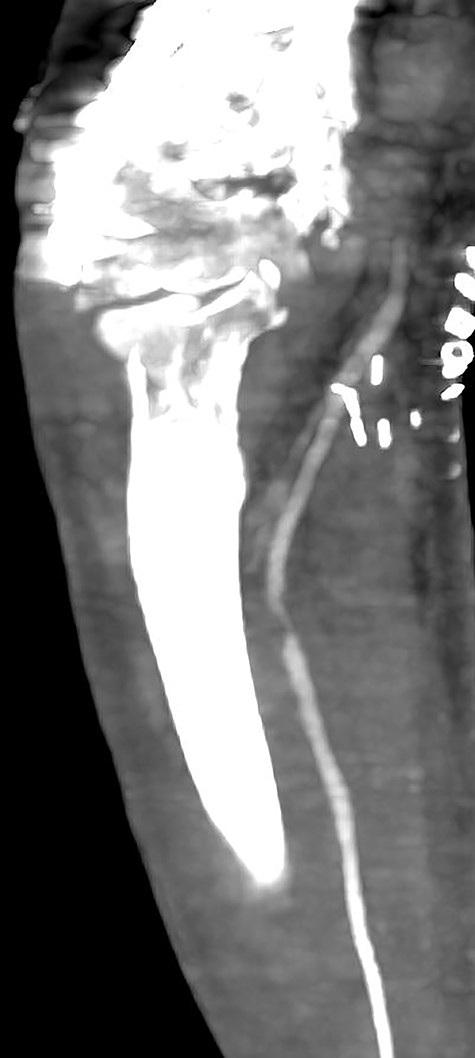

Seven days later, while his general condition was deteriorating, he developed acute ischemia in his right thumb and index finger (Fig. 2). In the ipsilateral forearm, a radial artery catheter had been inserted for monitoring. An urgent radial artery embolectomy was performed and restored the arterial supply to the right hand. The antithrombotic agent was changed to fondaparinux (7.5 mg/once daily). However, within the next few days, it was clinically evident that the revascularization effort was unsuccessful as the thumb and index finger developed dry gangrene. On examination, there was no palpable radial pulse, the ulnar artery pulse was palpable at the level of the wrist and the capillary refill time was normal at the middle, ring and little fingers. A CT angiography (Figs 3 and 4) was performed, demonstrating complete thrombosis of the radial artery beginning at the level of the elbow as well as a 70% occlusion of the ulnar artery ~15 cm proximal to the wrist. Thrombosis of the right axillary vein was also seen (Fig. 5). Orthopedic review was requested for consideration for finger amputation with a recommendation for arm amputation at the level of the elbow. Unfortunately, the patient died 72 h later from respiratory failure following a 24-day admission in ICU.

CT angiography of the right upper limb with volume rendering showing complete radial artery thrombosis beginning at the level of the elbow at the same level that embolectomy was performed. Also, there was significant ulnar artery stenosis near occlusion, ~15 cm proximal to the wrist. The ulnar artery appeared to be normal peripherally to the level of obstruction, with no collaterals being visible.